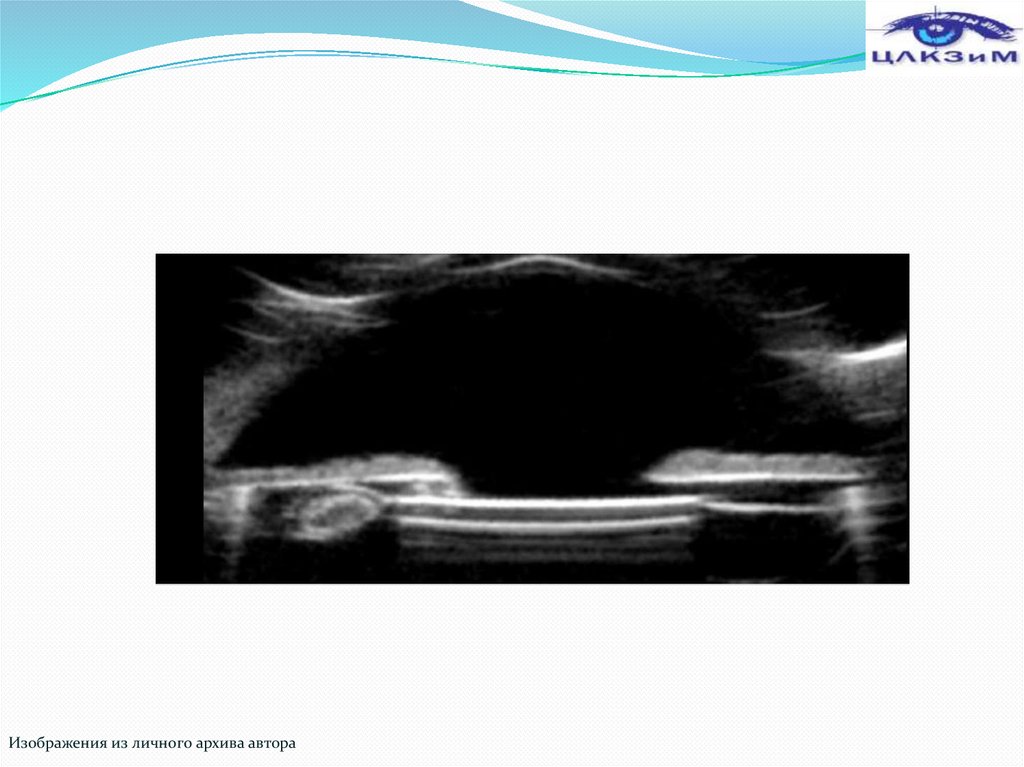

Изображения из личного архива автора